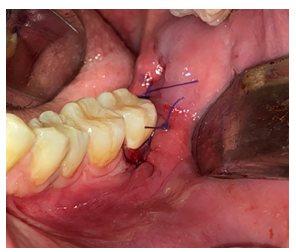

En boca del paciente se realizó PAAF (Punción por aspiración de aguja fina) obteniendo secreción hemática, de aproximadamente 1 CC, luego de descartar una lesión vascular se procedió a la toma de muestra para biopsia incisional de hueso supracortical de la lesión, en región retromolar distal a UD 37 y fragmento de membrana quística. Al momento de realizar la incisión se evidenció gasto líquido de un color blanco amarillento.

Figura 6 Manejo quirúrgico de la lesión (A) Realización del PAAF, (B) Levantamiento del colgajo. (C) Toma de muestra para biopsia incisional de hueso supracortical de la lesión en región retromolar. Fuente: Historia Clínica. Especialización Cirugía Bucal ULAC-IDOLA. 2022.